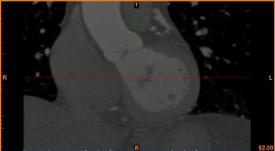

首先通过病人的心脏冠脉造影CT数据,获取病人的心脏冠脉三维模型。

病人的冠脉造影CT数据                                              提取出的冠脉三维数据